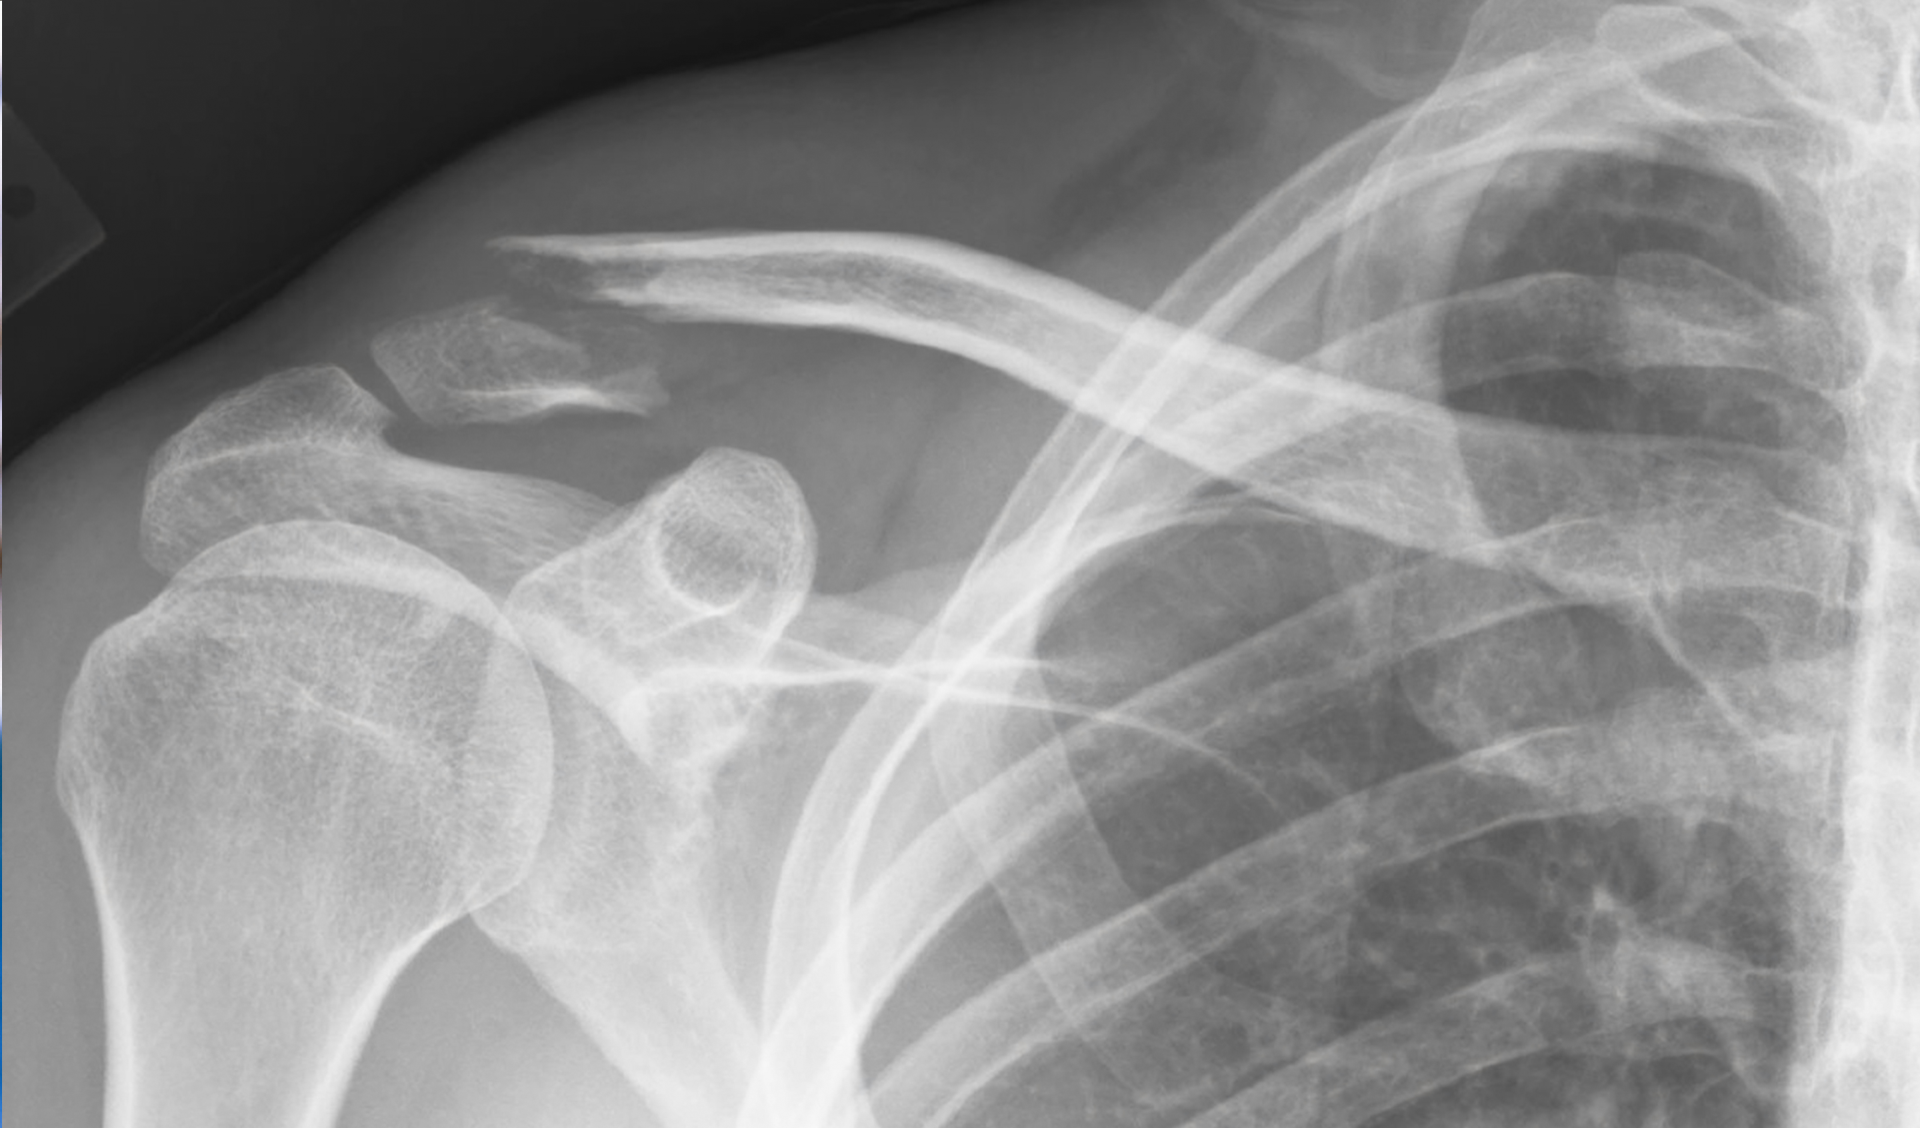

fracture | A fractured limb should be immobilized and the victim must immediately go or be taken to hospital. If there is a large swelling, a cold compress can be applied on the painful site. | In the case of open fractures, do not attempt to hide the protruding bone under the skin. Just rinse the wound with clean water and immediately call the ambulance service. |